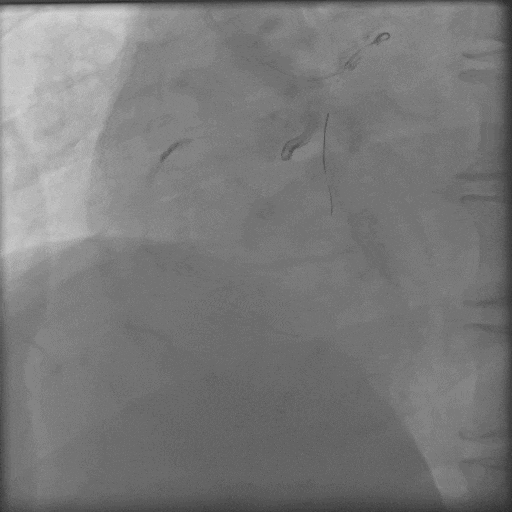

换用P200,导丝幸运进入血管真腔,

导丝怎么扩秦川论剑|张勇:攻坚克难——解决器械难以通过的CTO病变之技术图谱_https://www.jmylbn.com_新闻资讯_第23张

导丝通过后,Corsair微导管耐心旋转无法通过,小球囊无法通过;

导丝怎么扩秦川论剑|张勇:攻坚克难——解决器械难以通过的CTO病变之技术图谱_https://www.jmylbn.com_新闻资讯_第24张

采用M12、CP8-20导丝挤压(未留影),再小球囊掘进联合BAM技术;

导丝怎么扩秦川论剑|张勇:攻坚克难——解决器械难以通过的CTO病变之技术图谱_https://www.jmylbn.com_新闻资讯_第25张

Corsair微导管耐心旋转通过病变;

导丝怎么扩秦川论剑|张勇:攻坚克难——解决器械难以通过的CTO病变之技术图谱_https://www.jmylbn.com_新闻资讯_第26张

最终结果满意。